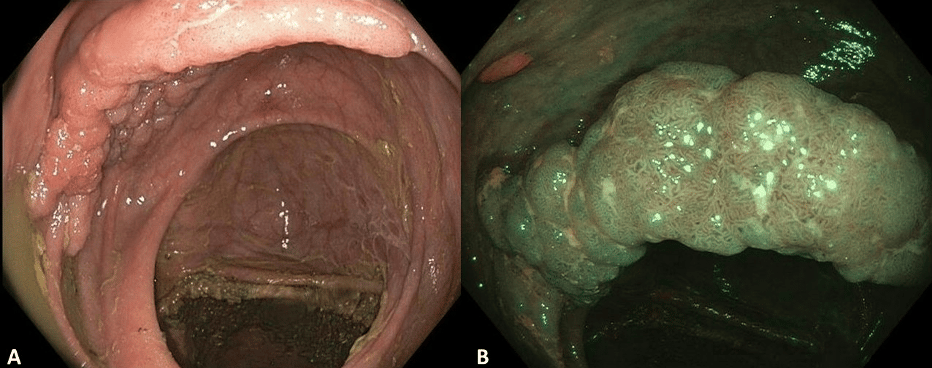

Quick Case: Laterally Spreading Tumor LST in Ascending Colon

Laterally spreading tumors (LSTs) are defined as nonpolypoid lesions ≥1 cm with lateral growth.

The two main categories of LST, based on their surface morphology, are granular (G) and non-granular (NG).

LAST-G have a low risk of containing cancer (approx. 10%)

LST-NG have the highest risk for covert cancer (approx one third).

The subtype of mixed LST with mixed features (GM-LSTs) have been poorly characterized, intermediate risk for covert cancer, about 10%. The risk of cancer on GM-LST varies by size, being twofold higher in lesions >4 cm than smaller lesions, and GM-LSTs in the rectum have a threefold higher risk than other locations to harbor covert cancer (1). The absolute risk for covert cancer was highest (22%) if the GM-LST was both rectal and ≥4 cm, compared with 5% to 8% absolute risk for other size and location combinations (1, 2).